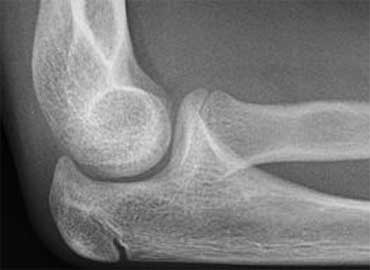

Capitellum fracture

While fractures of the lateral condyle occur in children between the age of 4 -10 years, isolated fractures of the capitellum are seen in children above the age of 12.

Capitellum fractures are uncommon.

The rotation of the fracture fragment gives a typical appearance on the X-rays (arrow).